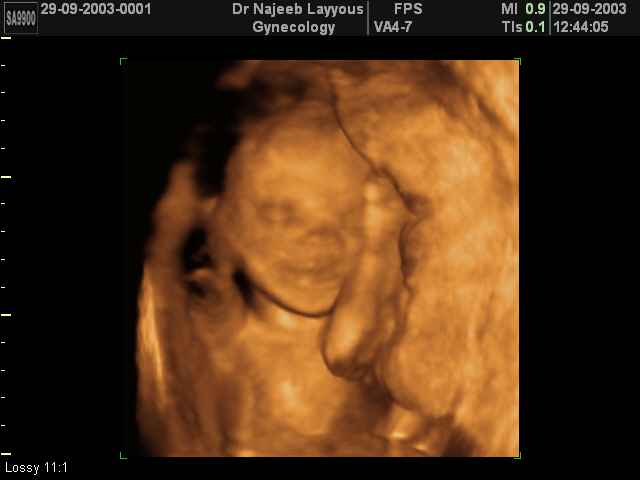

3D second trimestre échographie Photos de numérisation - deuxième partie de la grossesse | Dr N Layyous

3D second trimestre échographie Photos de numérisation - deuxième partie de la grossesse